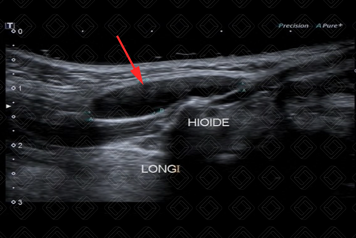

Texto alternativo para a imagem Figura 2. Créditos: Dra. Elazir Mota - Rio de Janeiro/RJ

Descrição das figuras 1 e 2: Ultrassonografia cervical. Lesão localizada na linha média da região cervical, com contornos bem definidos, anecoica, com reforço acústico posterior (seta vermelha). O osso hioide é uma referência anatômica importante e que deve ser descrito no laudo ultrassonográfico.

• Ultrassonografia cervical: Exame de escolha na avaliação dos cistos tireoglossos. A aparência ultrassonográfica é de uma lesão anecoica/hipoecoica, bem definida, com paredes finas, com reforço acústico posterior, na região cervical anterior, na linha média ou paramediana. A lesão pode ser hipoecoica devido a sangramento ou processo infeccioso associado. Em geral, não há vascularização ao color Doppler (figura 1);